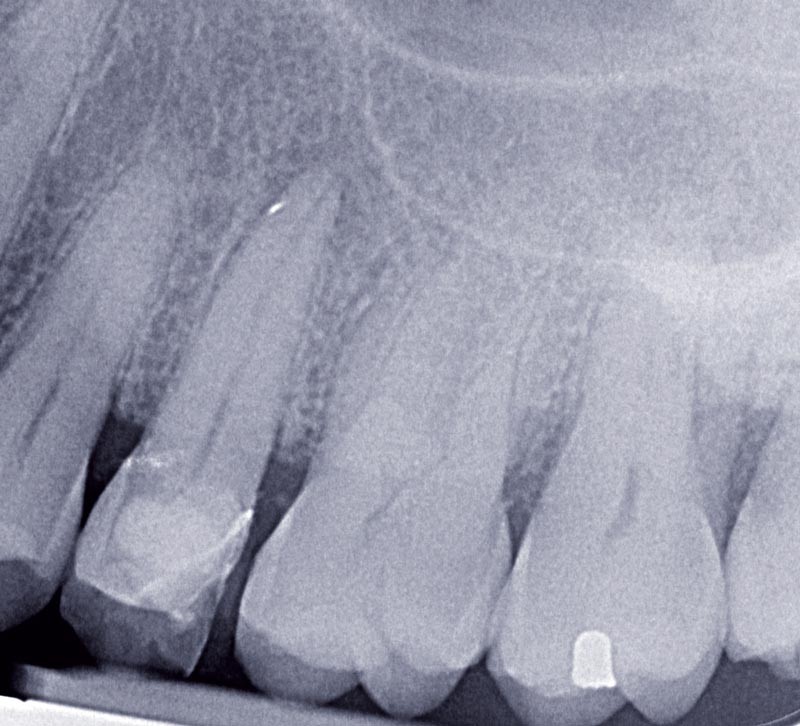

Nous avons abordé, dans l’article précédent (lID 3 du 22 janvier), comment élaborer une stratégie thérapeutique lors de la restauration d’une dent dépulpée. Les préparations dentaires pour le collage ne répondent plus à des catégories telles que la couronne, l’inlay, l’onlay ou la facette, mais répondent toutes à la définition de restauration adhésive (RA). Cette dernière présente des formes de préparation guidées par des paramètres fonctionnels, biologiques, mécaniques et esthétiques du matériau de restauration et de la dent. Nous allons finaliser notre restauration en décrivant les différentes étapes : de la communication avec le laboratoire au polissage de notre restauration.

Dès les étapes de préparation, nous avions décidé d’utiliser un matériau céramique. Il existe plusieurs familles de céramique disponibles pour réaliser des éléments prothétiques. Dans notre cas clinique, la céramique au disilicate de lithium (IPS e.max, Ivoclar Vivadent) est la plus appropriée en raison de sa capacité à être mordancée et donc collée, de sa résistance mécanique élevée et de sa mise en œuvre facile au laboratoire. Les procédés d’élaboration sont en revanche nombreux. La céramique peut être usinée ou pressée, monolithique ou stratifiée. Le choix entre la pressée ou l’usinée dépend essentiellement de l’équipement à la disposition du prothésiste. Mais les propriétés esthétiques et mécaniques ne sont pas les mêmes pour les différents procédés de fabrication. La fabrication de pièce IPS e.max par pressée permet d’obtenir des valeurs de résistance mécanique et de précision légèrement supérieures à la méthode usinée. Pour simplifier les étapes du laboratoire, il est possible de réaliser une couronne monolithique qui sera maquillée par la suite. Pour un résultat esthétique parfait et pérenne, l’utilisation d’une chape en IPS e.max stratifiée par la suite est la meilleure solution. Cette stratification peut être réalisée à partir d’un cut back ou recouvrir l’ensemble de la chape. Le cut back consiste à réaliser un fraisage périphérique de la couronne pour laisser de la place à de la masse de céramique émail.